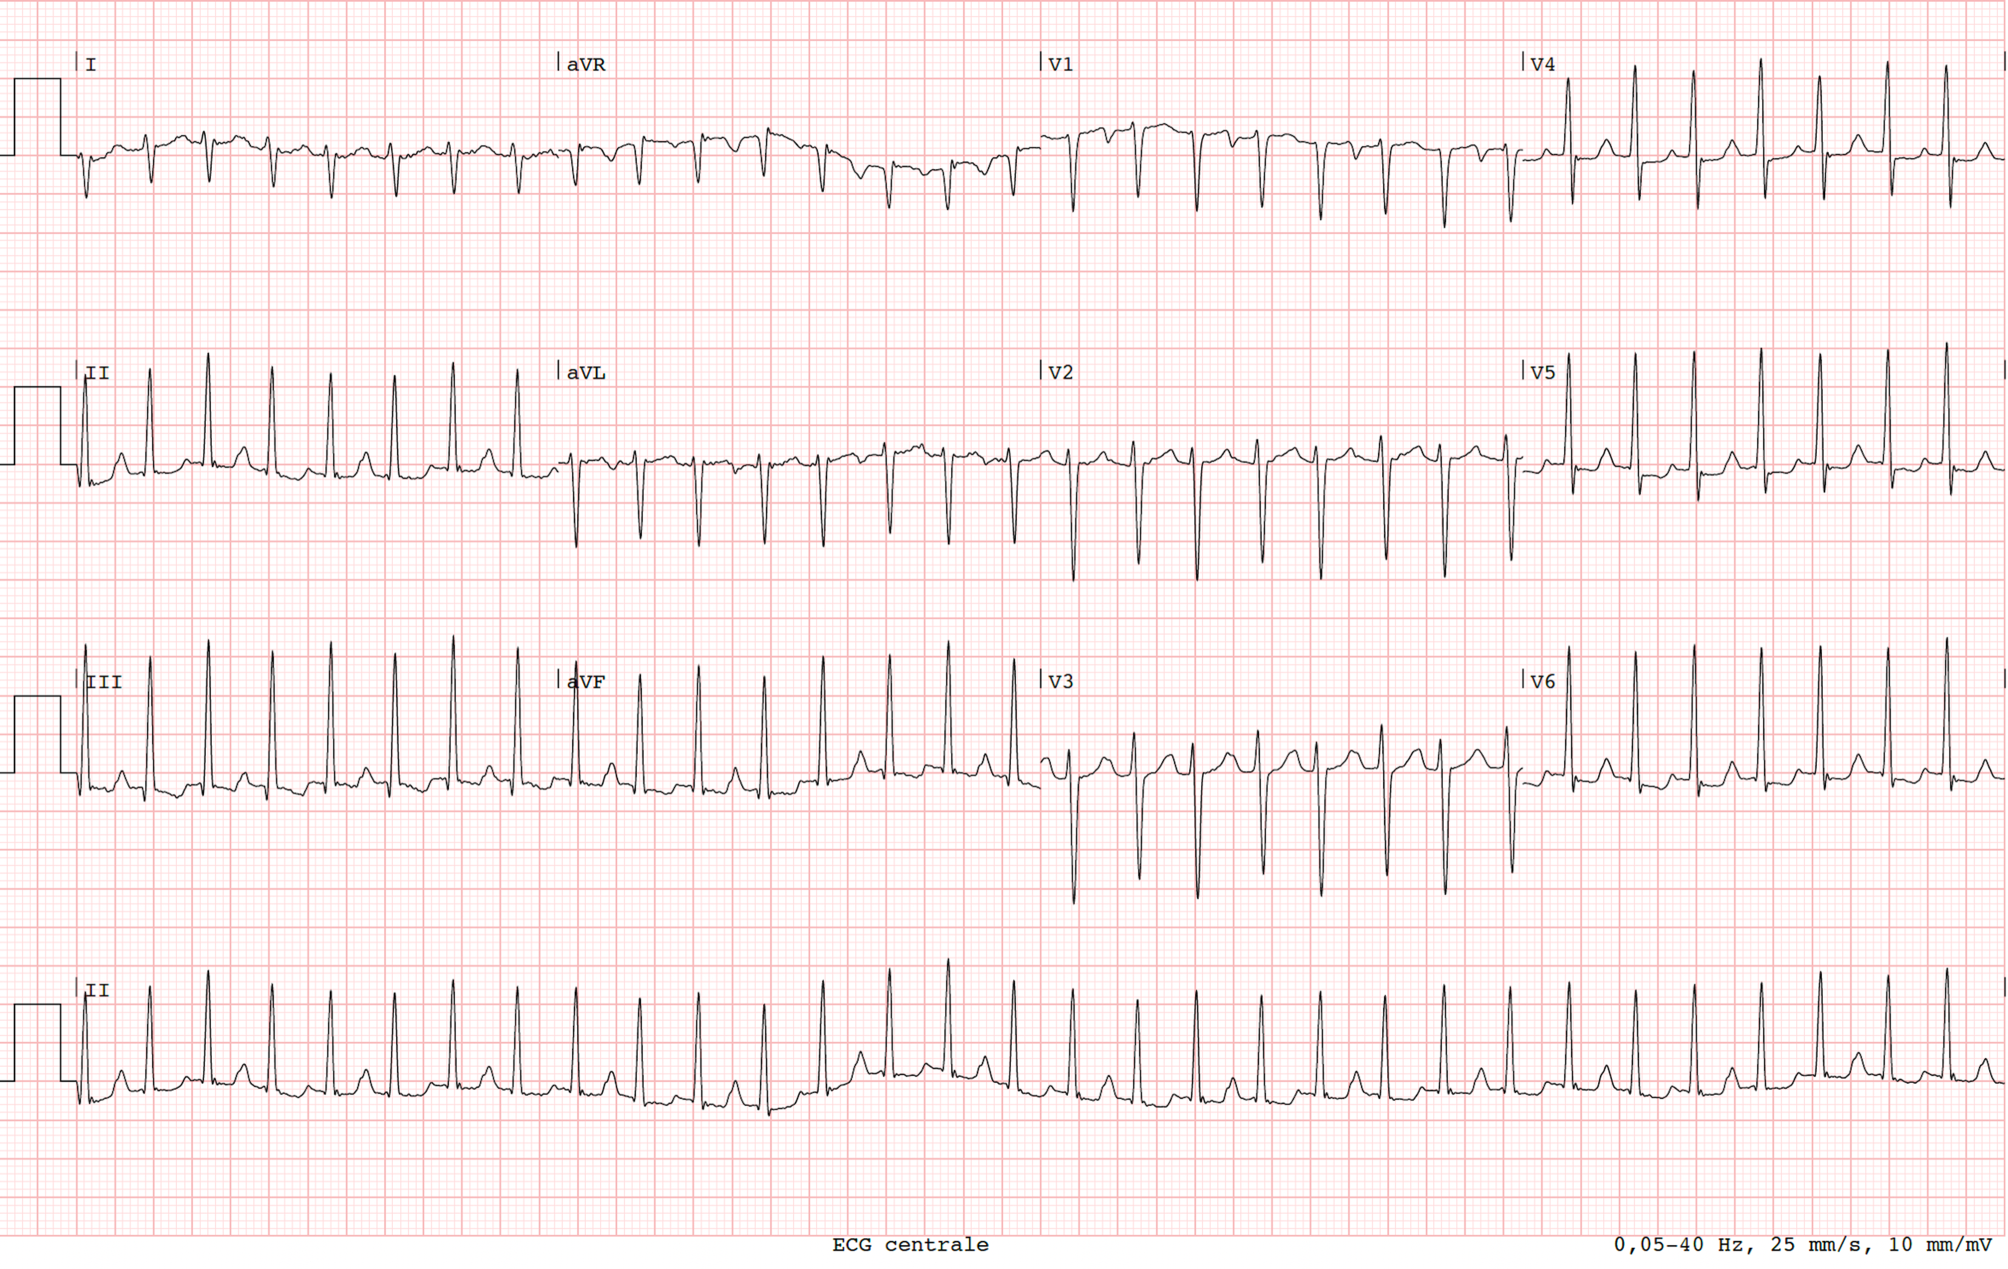

A 39-year-old woman presented to our emergency department with palpitations. She is known with premature atrial beats and a normal transthoracic echocardiogram. During the past year she developed palpitations, in particular following her pregnancy. Currently, she is not using any heart medication. Her family history was unremarkable. Her vital signs and physical exam were normal. Her initial ECG at the emergency department demonstrated a narrow QRS complex tachycardia of 186 beats per minute (Fig. 1). After 50 mg metoprolol, her heart returned to normal sinus rhythm (Fig. 2).

Fig. 1

Initial 12-lead ECG at the emergency department demonstrating a regular narrow QRS tachycardia

Fig. 2

The 12-lead ECG after metoprolol